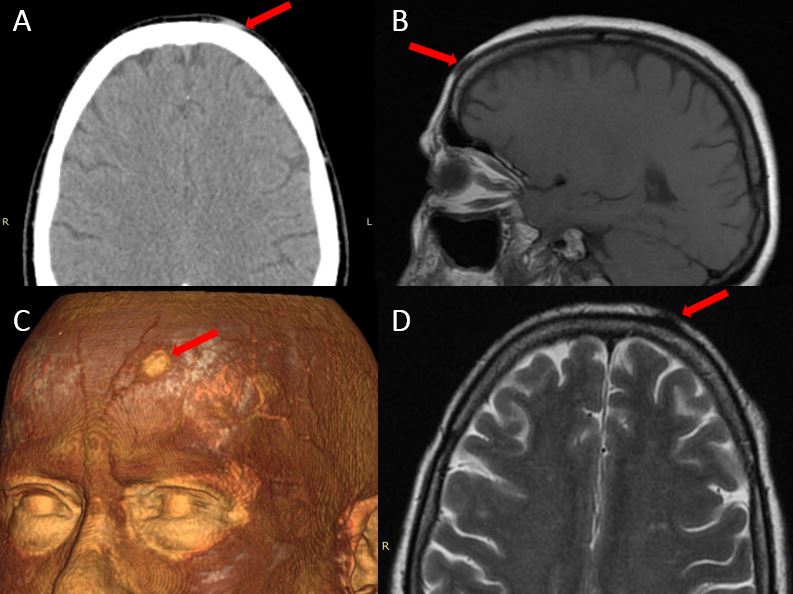

Пациентка была в плановом порядке направлена на хирургическое лечение. При осмотре кожи лба пациентки выявлен подкожный узел диаметром 1 см, выступающий над поверхностью кожи примерно на 4–5 мм. Кожа в области узла не изменена, не гиперемирована и безболезненна. Плотность узла умеренная, при надавливании несколько уплощается. По данным компьютерной и магнитно-резонансной томограмм пациентки гельминт в подкожном узле не идентифицировался (рис. 2). Со слов пациентки, этот узел образовался 2 года назад, а ранее подобные узлы появлялись и исчезали в разных участках волосистой части головы. При внешнем осмотре новых узлов на теле и голове не было обнаружено. В анамнезе у пациентки артериальная гипертензия и бронхиальная астма тяжёлого течения.

Рисунок 2. – Магнитно-резонансная (B,D) и компьютерная (А,С) томограммы пациентки. Крансая стрелка указывает на локализацию гельминта D.repens. А – компьютерная томография в аксиальной проекции; B – магнитно-резонансная томограмма в режиме T1 в сагиттальной проекции; С – трехмерная реконструкция компьютерной томографии головы; D - магнитно-резонансная томограмма в режиме T2 в аксиальной проекции.

Fig. 2. Computer (a, c) and magnetic resonance (b, d) tomograms of the patient: a — computed tomography in the axial view; b — magnetic resonance imaging in T1 mode in the sagittal view; c — 3-dimensional reconstruction of computed tomography of the head; d — magnetic resonance imaging in T2 mode in the axial view; the red arrow indicates the localization of the helminth D. repens.